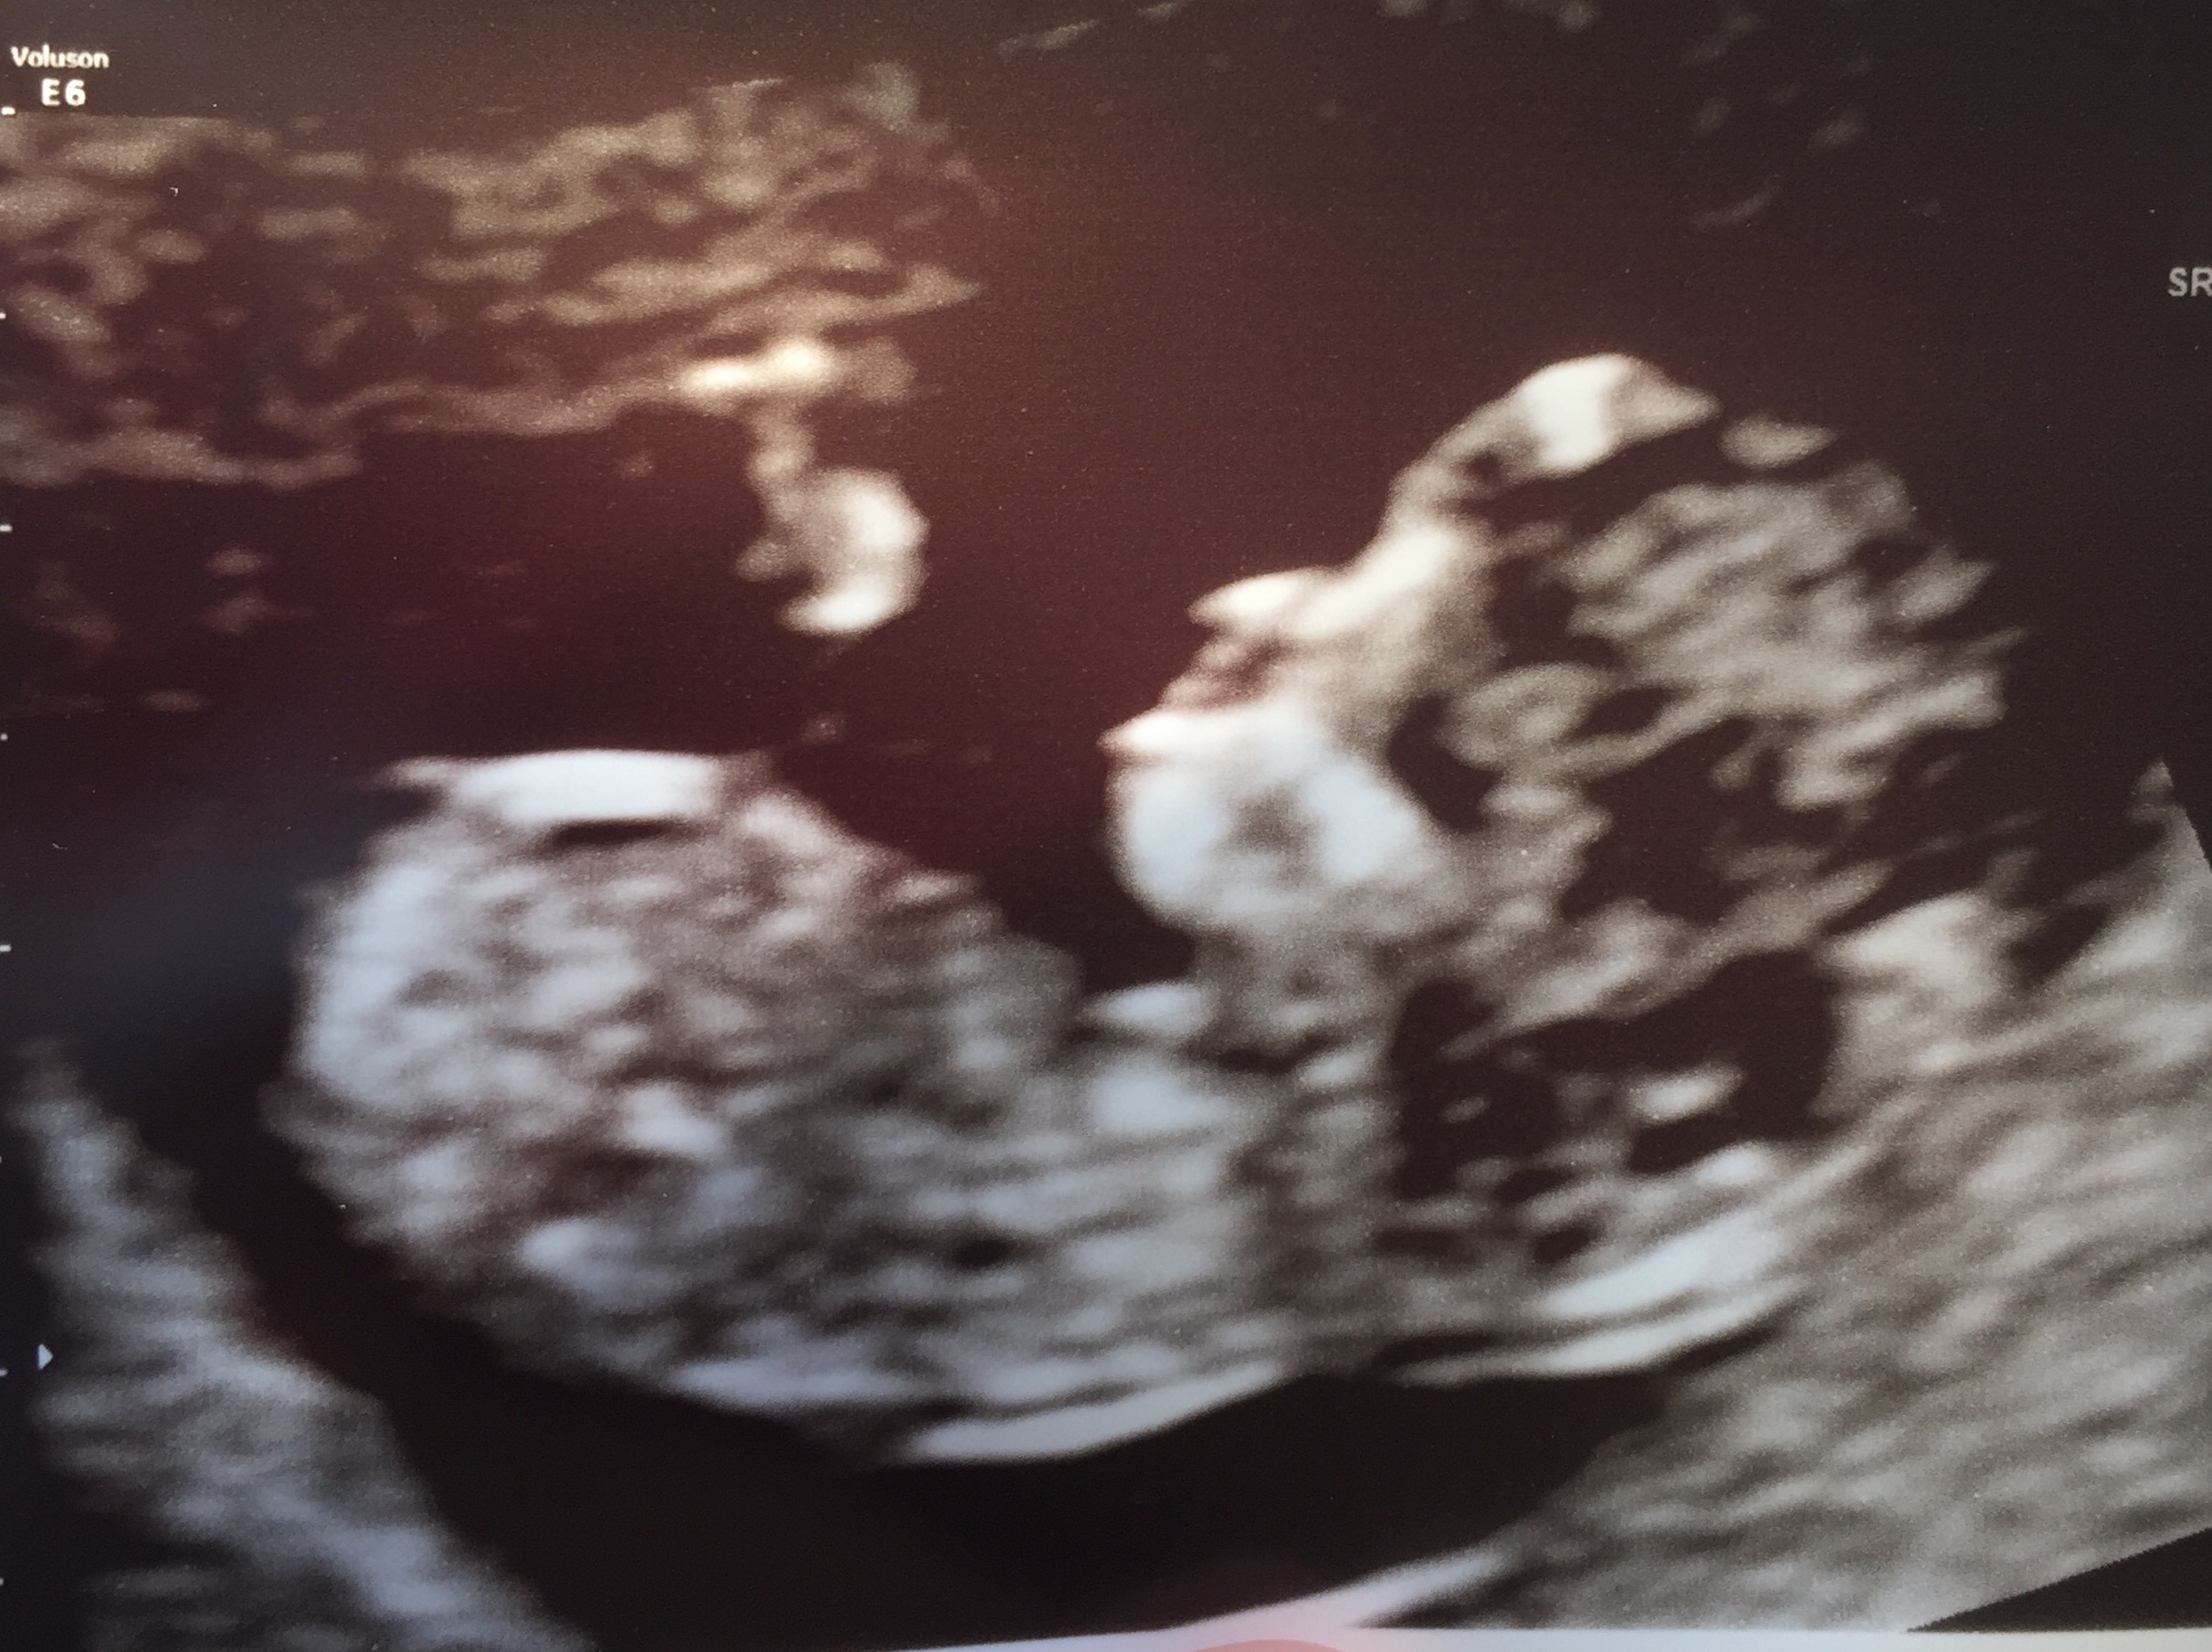

Hi! I had the NT ultrasound yesterday at 11 weeks 4 days. I had no idea about the skull theory until today, but I have an ultrasound pic that makes me curious. We'll find out the sex in two weeks since they do the genetic testing that tests for sex chromosomes as well. Any guesses in the meantime? Thanks in advance!